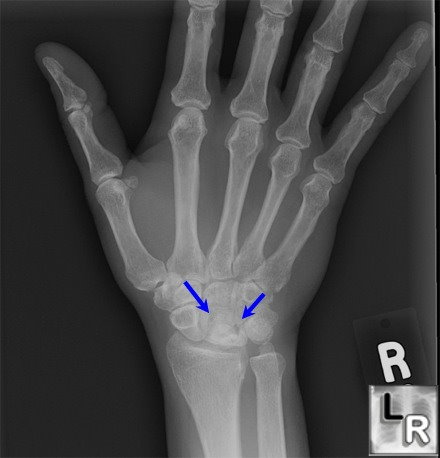

What is Kienböck’s disease?

Avascular necrosis of the lunate bone.

Who is most affected by Kienböck’s disease?

Young adults, often with negative ulnar variance or trauma.

What classification is used for Kienböck’s disease?

Lichtman Stages I–IV (MRI changes → sclerosis → collapse → arthritis).

Symptoms of Kienböck’s disease?

Wrist pain, stiffness, ↓ grip strength.

Radiographic findings in Kienböck’s disease?

Stage I – MRI changes; Stage II – lunate sclerosis; Stage III – collapse ± scaphoid rotation; Stage IV – arthritis.

Treatment options for Kienböck’s disease?

Immobilization, bone grafts, radial shortening/ulnar lengthening, proximal row carpectomy, wrist fusion.

What stage is this disease at?

Stage 4